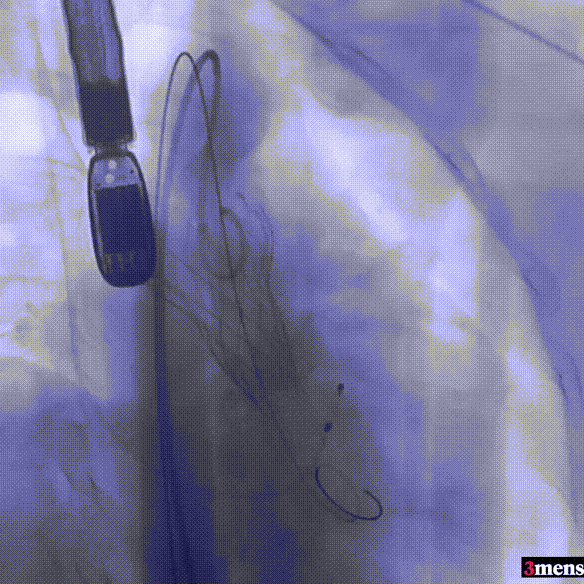

手术过程回顾:

患者全麻后,右侧股动脉建立主入路,主动脉根部造影显示主动脉瓣明显钙化。心室内轻微反流,主动脉及心脏情况整体较为稳定。直头导丝跨瓣后,在超硬导丝支撑下,瓣膜输送系统顺利跨瓣。在180次/分快速心室起搏下,确定降压至50mmHg后选择18mm球囊进行预扩张。在球囊扩张后,该患者血压未见升高,随即进行胸外按压,同时根据术前评估及球囊预扩情况,选取直径23mm瓣膜果断快速进行瓣膜定位并释放。瓣膜释放后患者心律和血压趋于平稳。

直头导丝跨瓣

球囊预扩

瓣膜定位并行胸外按压

瓣膜释放至工作位

瓣膜脱钩